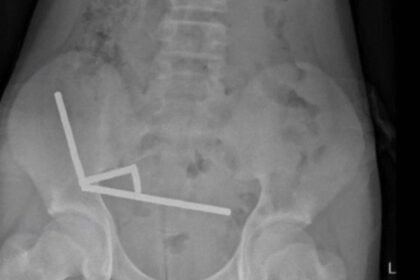

Yeni Zelanda’da 13 yaşındaki bir çocuk, neredeyse 200 yüksek güçlü mıknatıs yuttuktan sonra bağırsaklarının bir bölümünün cerrahi olarak alınması gerekti. Tauranga Hastanesi’nde karın ağrısı şikayetiy...